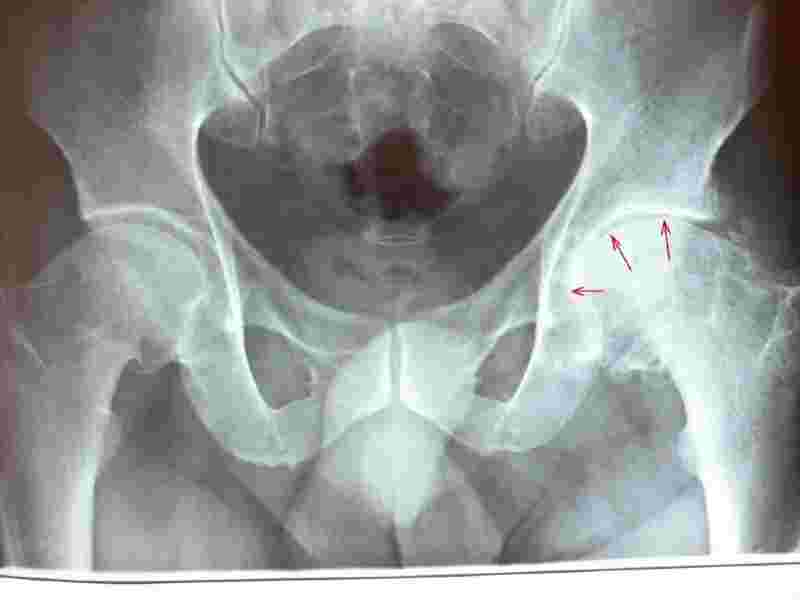

Enjoy It Again!!! Don't Roll Me A Joint! Joint replacements?

Joint replacements? Artificial hips, knees, shoulders? Not always so easy. There ARE dangers, which They never tell you about. They never get to Cause. At THE HARTE OF HEALTH, we deal with Cause. Can you avoid these surgeries?